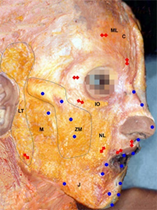

Topical anesthesia with lidocaine hydrochloride cream was applied on the facial zones for five minutes and cleaned with alcoholic chlorhexidine solution before the injection. Pinching-lifting the skin using the thumb and index to lift subcutaneous tissue away from the muscle layer were made to prevent vascular injury (Figure 1.). Bolus injection used a 27G½ needle in a perpendicular transcutaneous approach to inject a high-G' product, creating a pillar to project and lifting the central facial triangle. Retrograde-backflow injection used a 25G50mm blunt-tip cannula, excepting in glabella, philtral ridge and white roll where was used a 27G½ needle, to inject high-, medium- and low-G' products to volumetric expansion and modeling the face. The volume of HA per facial zone varied as the aging-changes.

Figure 1 Bolus injection by pinching the skin to lift subcutaneous tissue away from the muscle layer.

An individual approach for each facial zone related to points, technique and location of the injections, and adequate HA-products created a safety protocol for FR-HA (Figure 2).

Figure 2 Blue points indicate bolus injection. Red points and lines retrograde-backflow injection.

Superficial fat compartments: middle-lateral (ML) and central (C), infraorbital (IO), nasolabial (NL), zygomatic-malar (ZM), middle (M), lateral-temporal (LT), and jowls (J).

Forehead: Retrograde-backflow technique pointed on each horizontal line injected SubQ-product in the superficial central and middle-lateral fat compartments.

Glabella: Retrograde-backflow technique pointed on the caudal end of vertical line injected Fine-product intradermally.

Crow's feet: Retrograde-backflow technique pointed on the lateral end of each wrinkle injected Deep-product subcutaneously.

Tear trough and Nasojugal groove: Retrograde-backflow technique pointed 1 cm below the inferior-lateral orbital rim injected Fine-product in the superficial infraorbital fat compartment.

Cheek: Bolus technique pointed on the zygomatic arch, zygomatic prominence, antero-medial cheek, lateral-cheek and buccal zone injected SubQ-product in the superficial zygomatic-malar and middle fat compartments.

Nasolabial fold: Retrograde-backflow technique pointed on the caudal end of the nasolabial fold injected SubQ-product along the superficial nasolabial fat compartment.

Marionette lines: Bolus technique pointed on the modiolus, and middle of the hollow injected SubQ-product subcutaneously.

Chin: Retrograde-backflow technique pointed on mental crease end and bolus technique pointed on the lateral borders and midpoint of the chin injected Deep-product subcutaneously.

Jowls: Bolus technique pointed on the jowls sulcus injected Deep-product in the superficial jowls fat compartment.

Jawline: Retrograde-backflow technique pointed at the jaw angle injected SubQ-product downward in the superficial middle fat compartment and upward in the superficial lateral-temporal fat compartment.

Lip: Retrograde-backflow technique pointed on white roll injected Deep-product, in the philtral ridge, subcutaneously, and Fine-product in white roll and cupid's bowl by retrograde-backflow technique, subcutaneously, and as bolus technique in the vermillion submucosa.